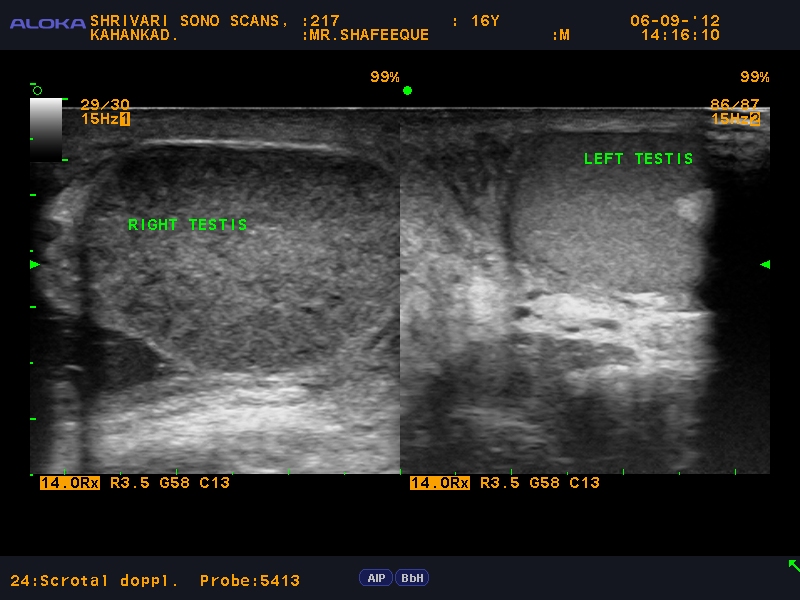

From shrivariscans.blogspot.com

Shrivari Sono Scans Ultrasound images in acute scrotumTorsion Testis Testicular Torsion On Ultrasound Although ultrasound is the choice modality for evaluating the potentially torsed testis it is not helpful for. our goal is to illustrate key sonographic features in the spectrum of. prompt doppler ultrasonography to aid in diagnosis is often key to managing testicular torsion, but there may be delays in. testicular torsion is a twisting of the spermatic. Testicular Torsion On Ultrasound.